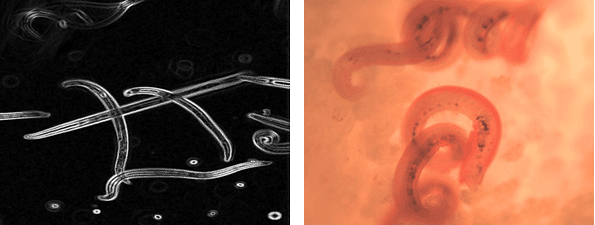

Allergic inflammation is characterized by the infiltration of tissues by eosinophils and basophils, which are normally rare myeloid cells that comprise only a few percent of circulating blood cells. The adaptive allergic immune response is characterized by increases in the numbers of Th2 cells that release interleukin-4 (IL-4) and IL-13 and the development of plasma cells that secrete immunoglobulin E (IgE). When sustained, these responses can lead to alterations at mucosal epithelial surfaces, including increases in the number of mucus-secreting cells and increased deposition of collagen in the tissues. These responses can be protective in healing the epithelium from attack by parasitic worms, such as hookworms and schistosomes. When these types of immunity become focused on common environmental exposures, however, such as inhaled dust mites or mold or consumed shellfish, the result can be allergies, including potentially life-threatening afflictions such as asthma and food allergy, which affect, respectively, more than 20 million and 2 million Americans.

Despite advances in our understanding of the immune system, relatively little is known about substances in allergens that invoke the constellation of cell responses we call allergic immunity. Our laboratory developed mice with a fluorescent reporter—green fluorescent protein—placed into the il4 gene, allowing us to track cells capable of secreting IL-4 in vivo. IL-4 and its companion, IL-13, are necessary for allergic immunity, and we could use this system to begin to understand how these cytokines are induced during immune reactions in the living mouse. Using a parasitic worm infection or a mouse model of allergic lung inflammation, we were able to identify eosinophils, basophils, and Th2 cells in tissues in response to the challenge. None of these responses occurred in mice that lacked IL-4 and IL-13, confirming that these two cytokines are essential for both defense against helminths and for the development of allergic immunity.

To test this, we administered chitin to the lungs or peritoneum of mice and analyzed the cells present in the tissues. Beginning as early as 3 hours and peaking by 48 hours, eosinophils and basophils entered tissues where chitin was present. If the chitin was first digested with the recombinant chitinase, AMCase, and then given to the mice, no allergic inflammation resulted, suggesting that intact chitin is required for the response. We confirmed this by creating transgenic mice that overexpressed AMCase in the lung at levels induced after helminth infection. These mice were unaffected by the increased levels of AMCase but, when treated with chitin, they did not develop tissue eosinophils and basophils to the same extent as control mice. Finally, when the natural lung AMCase was neutralized using antibodies, the eosinophils and basophils persisted longer in tissues. These findings suggest that the IL-4 and IL-13 response induces epithelial chitinase, which in turn degrades the chitin, thus relieving the stimulus for the allergic response.